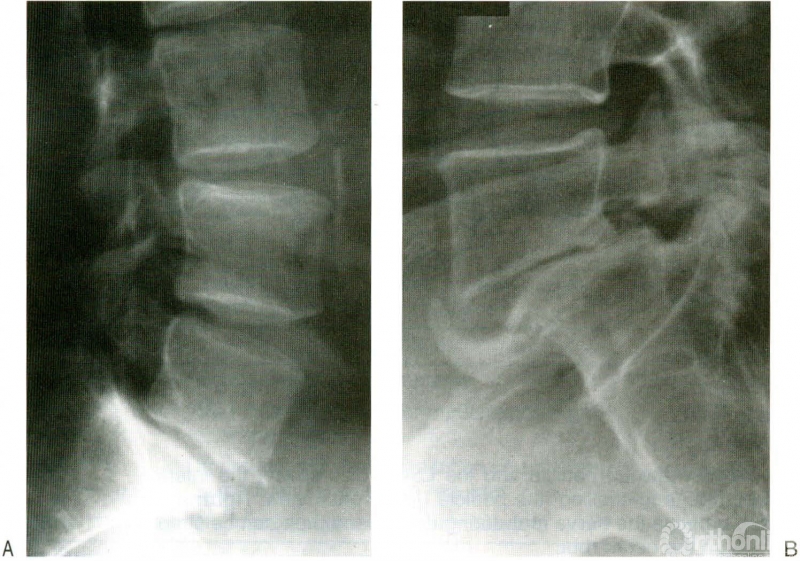

1、 L5峡部有断裂(图1);

图1 A:L5-S1稳定的峡部裂性腰椎滑脱(“稳定”意味着患者无腰痛,腰椎屈伸动力位片没有移位);B:非常稳定的L5-S1滑脱,由于退变引起了L5椎间孔的狭窄。